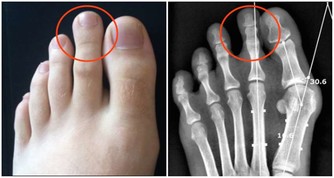

3. 你的腸道裡有寄生蟲

大便中的白色斑點也可能是絛蟲或蟯蟲。雖然如今絛蟲感染並不常見,但依然有可能。如果看到白色或黃色的斑點,可能就是絛蟲,它們通常是扁平的、方形的,大小與米粒相當。有些人可能沒有症狀,但有些人可能出現胃痛或腹瀉。人們通常是因為吃生的或未煮熟的肉而感染絛蟲。絛蟲感染比較好治療,一粒藥丸就足以殺死絛蟲,它會從糞便中排出體外。

蟯蟲感染更常見,特別是在兒童中。蟯蟲很小,是白色的,大小和訂書針一樣大。

它們通常看起來像白線,所以也被稱為線蟲。

蟯蟲通常生活在腸道的下部,並在肛門周圍的皮膚上產卵,這可能會導致肛門不適和瘙癢。